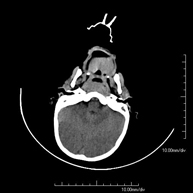

- Neurorradiología- TC Cráneo Prueba radiológica que consiste en obtener imágenes del cráneo de alta definición anatómica (tronco cerebral, cerebelo, cerebro, calota craneal, etc.), mediante el empleo de un equipo de TC (Tomografía Computarizada).Indicaciones: traumatismos, cefalea, trastornos de la memoria, pérdida de fuerza súbita en una extremidad o mitad del cuerpo. Prueba radiológica que consiste en obtener imágenes del cráneo de alta definición anatómica (tronco cerebral, cerebelo, cerebro, calota craneal, etc.), mediante el empleo de un equipo de TC (Tomografía Computarizada).Indicaciones: traumatismos, cefalea, trastornos de la memoria, pérdida de fuerza súbita en una extremidad o mitad del cuerpo.